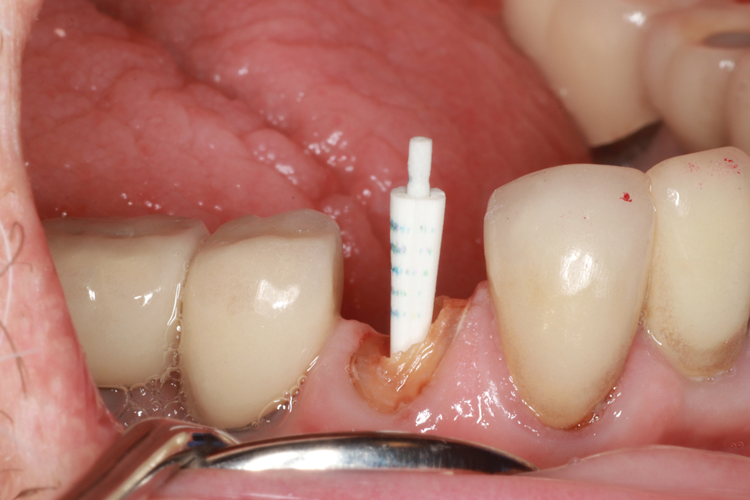

(5.) Prepared tooth with an oval shaped access before and after insertion of an oval-shaped post.

Figure 5

Oval-Shaped Fiber Posts

For oval-shaped canals, posts with an oval-shaped coronal two-thirds and a tapered, round apical one-third have been introduced. The oval-shaped section reduces the amount of coronal space that needs to be filled in and increases the flexural strength of the post in that region (Figure 5). These posts are useful adjuncts, providing better adaptation13 and increased fracture resistance.14 Similar to other available systems, oval-shaped post systems require separate, specific instruments to accommodate and fit the various sizes.